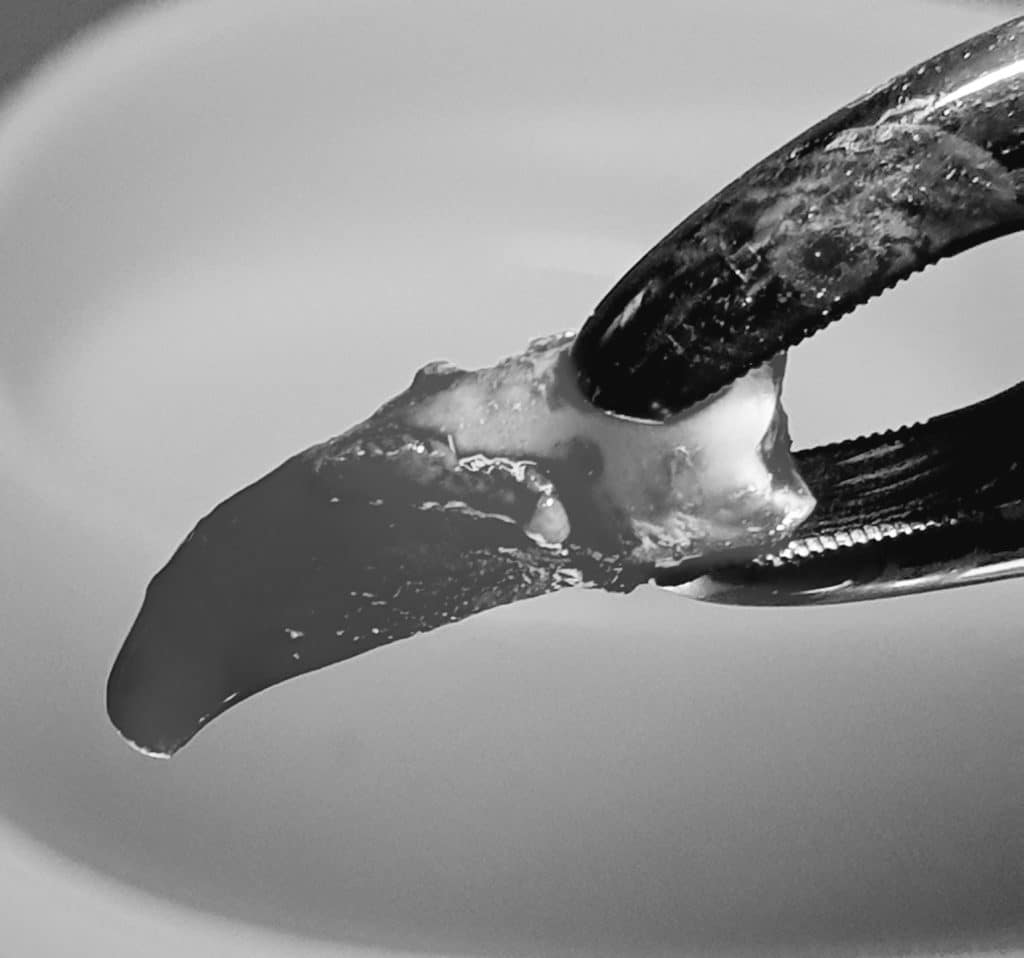

L’estrazione è stata portata a termine con successo, il dente ha presentato radice curva e nella zona interessata dell’estrazione si è provveduto a inserire spugnetta emostatica ed osso sintetico e sutura.